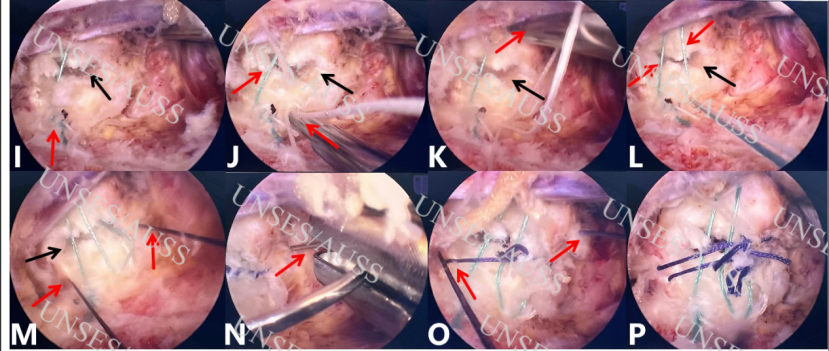

图3 硬膜囊缝合,纤维环“井”字型四针缝合手术步骤(2)I收紧白线,可自动打紧第一个结,应用推结器由体外到体内继续推入两结,剪线器剪线,第一针缝合完毕;J-K第二针缝合方式同第一针,在第一针尾侧2mm平行于第一针进行缝合;M-O应用4-0可吸收带线针,垂直于纤维环破口纵轴缝合,进、出针点位于破口两侧(头尾侧)2mm处。由体外至体内打三结,推结器推结,剪线器剪线,第三针缝合完毕。平行于第三针靠中线侧2mm处进行4-0可吸收带线针第四针缝合,垂直于纤维环破口纵轴缝合,进、出针点位于破口两侧2mm处。由体外至体内打三结,推结器推结,剪线器剪线,第四针缝合完毕;P纤维环“井”字型四针缝合。